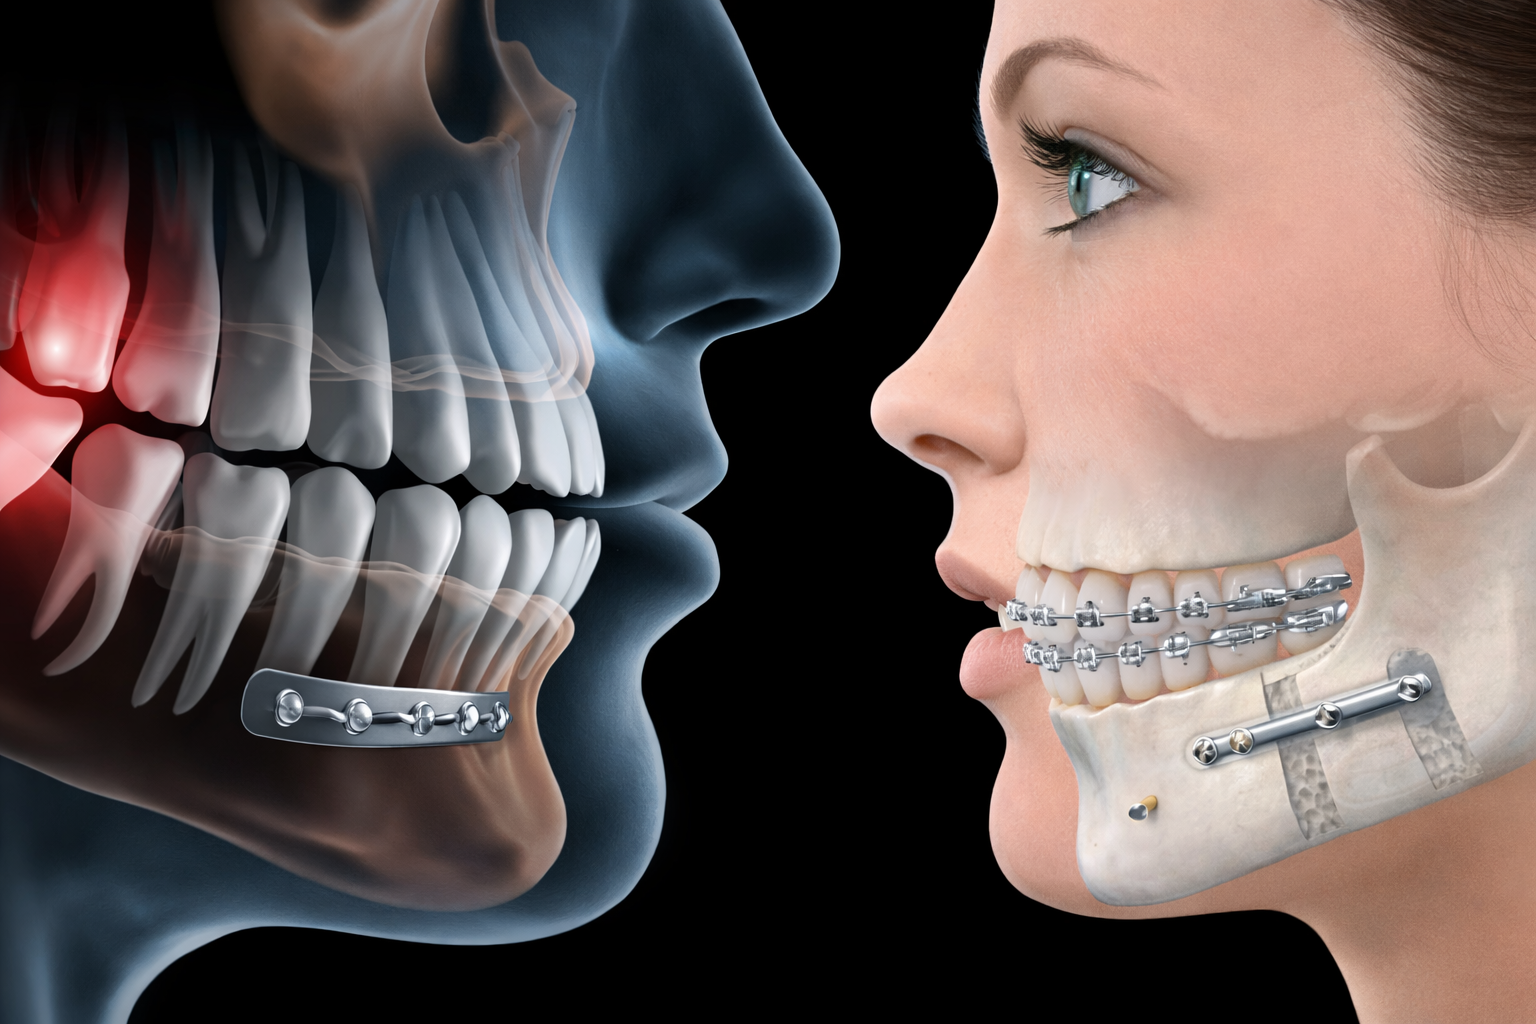

Endodonti , dişin iç kısmında bulunan pulpa (sinir-damar dokusu) ve kök kanalları ile ilgili hastalıkların tanı ve tedavisini yapan daldır

Temel amacı, ileri derecede hasar görmüş dişleri çekmeden ağızda tutmaktır.

- Çürük veya travma nedeniyle hasar görmüş dişlerin tedavisi

- Enfekte pulpanın temizlenmesi

- Kök kanallarının şekillendirilmesi ve doldurulması

- Kanal tedavisiyle iyileşmeyen enfeksiyonların cerrahi tedavisi

- Kök ucundaki iltihaplı dokuların temizlenmesi

- Dijital radyografi ve CBCT değerlendirmeleri